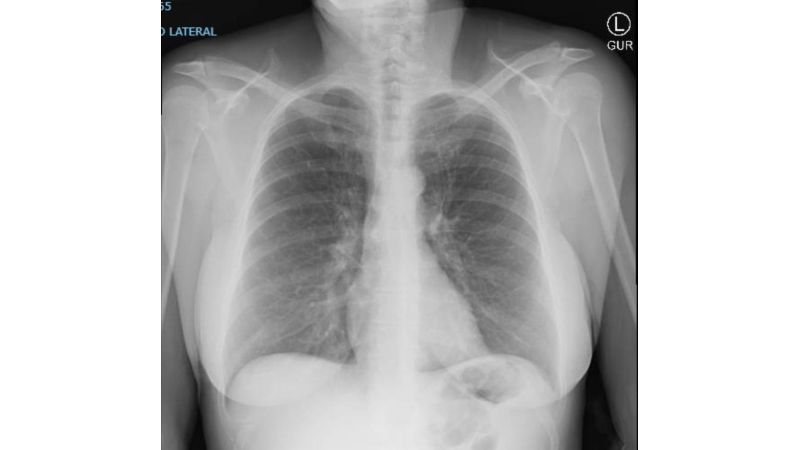

Feb 14 2024 X-Ray Rounds - Lecture Slides

Chest radiology

Clinical radiology

Radiology

Respiratory medicine